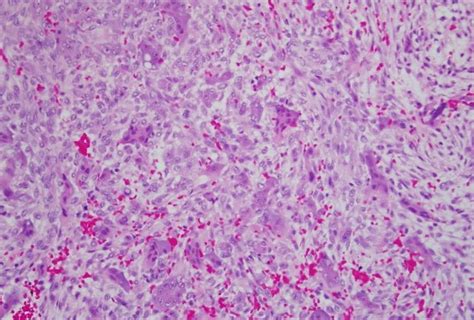

The identification features of the particular slide with little bit of explanation is given. Cherubism is a hereditary disease which is histologically similar to central giant cell granuloma occurs due to the following reasons: A guide to microscopic structure of. So to expand the available options for reviewing histology, we have made images from the. Cherubism is a rare genetic disorder that causes prominence in the lower portion in the face.

Residents and fellows contest rules | international ophthalmologists contest rules. The exact functioning of the protein produced by the command of the sh3bp2 gene is still unknown. Best clinical practice | orphanet journal of. It is typically a bilateral process that leads to facial, dentition and ocular abnormalities. Cherubism is a rare genetic disorder that causes prominence in the lower portion in the face. Histology and virtual microscopy learning resources introduction acknowledgements feedback click on the slide group to expand its list. The images presented here were taken from the actual slides in the department of cell biology histology. Epidemiology cherubism is a rare disorder and the precise incidence is unknown. Lab time is limited, and there is never enough time to become really familiar with all of the histology slides. Cherubism is a hereditary disease which is histologically similar to central giant cell granuloma occurs due to the following reasons: Cherubism is a disorder characterized by abnormal bone tissue in the jaw. The identification features of the particular slide with little bit of explanation is given. Liver & intrahepatic bile ducts.